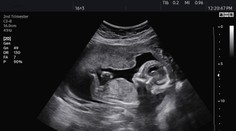

Ženám s PCOS chýba kľúčová baktéria v čreve (ilustračná snímka)

Ženám s PCOS chýba kľúčová baktéria v čreve (ilustračná snímka) Zdroj: Profimedia